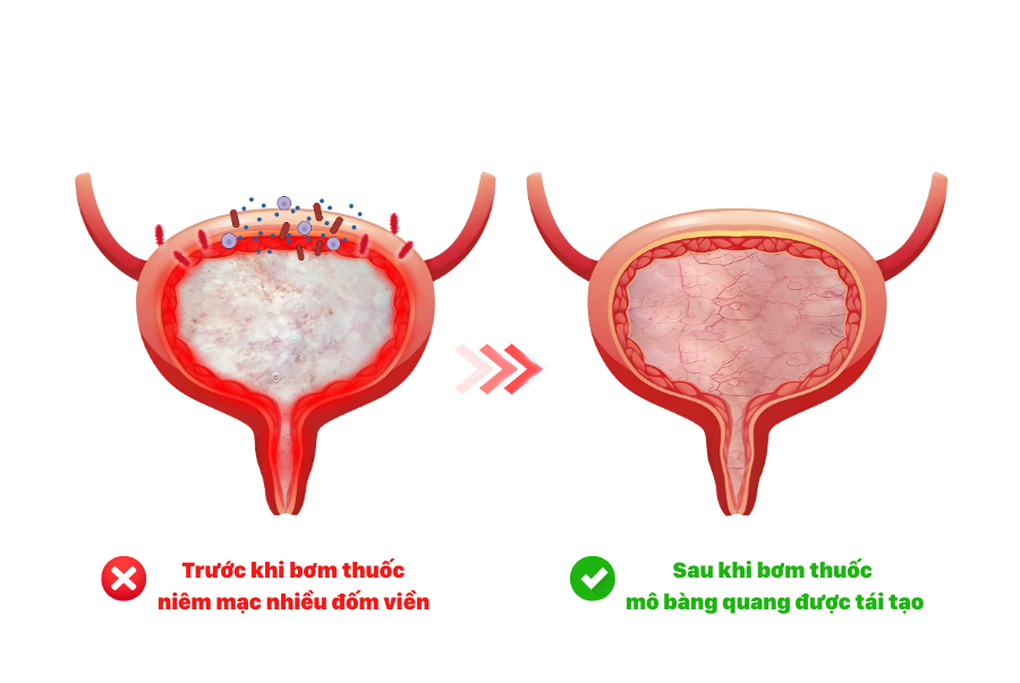

Trên cơ sở đó, bác sĩ đã chỉ định cho bệnh nhân thực hiện phương pháp bơm chất nhờn bàng quang nhằm tái tạo lớp niêm mạc bảo vệ, phục hồi hàng rào sinh học tự nhiên và hạn chế sự bám dính của vi khuẩn. Đây là phương pháp không cần phẫu thuật, được thực hiện nhẹ nhàng và an toàn.

Sau liệu trình 7 lần bơm trong 3 tháng, lớp niêm mạc bàng quang sẽ được phục hồi rõ rệt, tình trạng viêm giảm dần, các triệu chứng tiểu buốt, tiểu rắt, đau tức hạ vị thuyên giảm đáng kể. Khi hàng rào bảo vệ được tái tạo, bàng quang trở nên ổn định hơn, giúp hạn chế tái phát viêm và cải thiện chất lượng cuộc sống người bệnh.

Hiệu quả sau bơm thuốc, thành bàng quang dày, khỏe mạnh (Ảnh: BVCC).